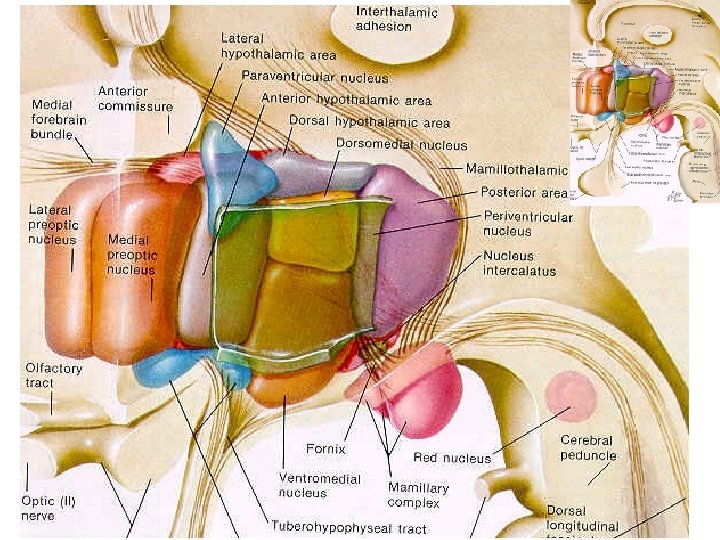

Hypothalamus

Hypothalamus • • je derivát visceromotorické zóny bazální ploténky nejvyšší autonomní ústředí infundibulum + hypophysis tuber cinereum (eminentia mediana) + corpus mammillare • area preoptica + chiasma et tractus opticus

Hypothalamus • infundibulum • tuber cinereum • corpora mammillaria • recessus infundibuli • recessus opticus

Hypothalamus – ohraničení • • nahoře: sulcus hypothalamicus dole: viditelný na dolní ploše mozku vpředu: lamina terminalis vzadu: přechází do tegmentum mesencephali • mediálně: 3. komora • laterálně: capsula interna

Hypothalamus 3 podélné zóny: periventrikulární, mediální, laterální zóna 3 příčné zóny: přední, střední, zadní hypothalamus Nuclei • přední hypothalamus (area hypothalamica rostralis) - nucleus paraventricularis, supraopticus, suprachiasmaticus • střední hypothalamus (area hypothalamica intermedia et dorsalis) nuclei tuberales laterales et ventromediales • zadní hypothalamus (area hypothalamica posterior) - nuclei mammillares, nucleus h. posterior, nucleus tberomammillaris